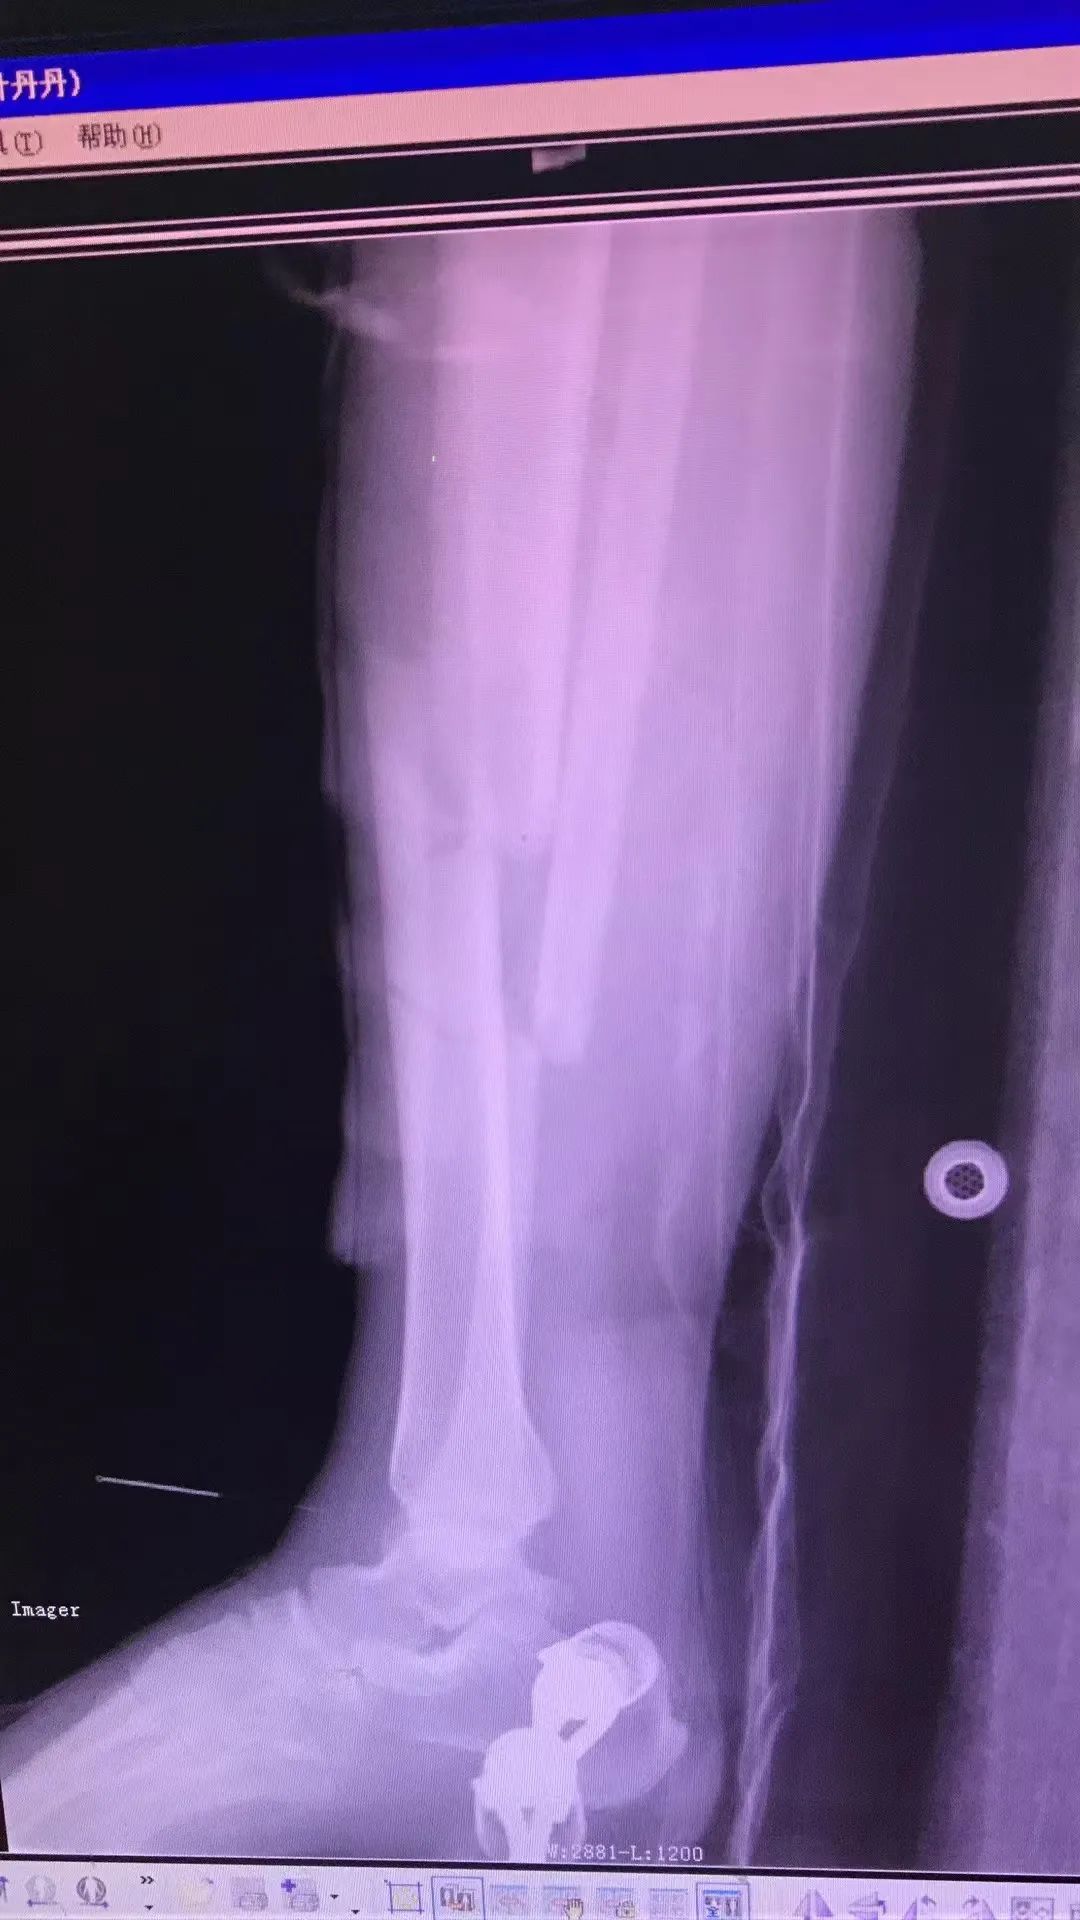

夫妻遭遇车祸,双双造成粉碎性骨折 八年前,唐女士夫妻俩曾经营着一家小商店,7月的一天,丈夫骑着摩托车带着她在前往门市的路上,被一辆小货车直接撞飞,然后俩人被重重的摔在了地上。“痛到麻木,我当时就想肯定完蛋了。”唐女士回忆到。 事故发生后,肇事司机立即拨打了急救120,唐女士夫妻随即被送到了就近的综合医院,经过全面检查,夫妻俩均被诊断为“胫腓骨粉碎性骨折”。“当时觉得特别有意思,我俩骨折的地方一模一样。”唐女士笑着说。 (唐女士第一次片子) 拒绝手术,转院寻求中医治疗 “当时医院建议我们手术,被我拒绝了。”唐女士回忆,由于害怕手术风险及后遗症,果断拒绝了手术治疗方案,而后通过多方了解,夫妻俩转院到了成都八一骨科医院。入院后,医院骨七科副主任医师叶丹丹作为唐女士的主治医生,对她的印象非常深刻。“当时考虑到患者的特殊性,科室专门调整了一个双人病房给唐女士夫妻。” 治疗上,叶丹丹医生采用“何天佐传统中医药正骨疗法”为唐女士夫妻进行手法复位,并辅以牵引疗法及外敷中药进行纯中医治疗。“效果非常好,8年过去了,我的腿没有任何后遗症!”准妈妈唐女士的脸上洋溢着幸福的笑容。 “医”心为患者,“医患”变朋友 八年前,不到30岁的唐女士与丈夫双双住院,家中两位老人不但要照顾两个病人,还要照顾家中两个小孩儿。唐女士看着老人们来回奔波,心里十分过意不去,住院治疗期间变得十分焦虑与不安。同为女性的叶丹丹医生看在眼里,尽己所能的为唐女士一家提供生活上的便利,并努力的帮助他缓解焦虑不安的不良情绪。“叶医生对我就像朋友一样,非常幸运能遇到这么好的医生。”唐女士说道。 住院治疗3个月后,唐女士及丈夫顺利出院。出院后,叶丹丹医生通过线上的方式,时刻为唐女士解疑达惑,居家康复应该怎么做?生活上有哪些注意事项?等等。八年时间里,俩人的话题也从医疗问题延伸到了各自的家庭与生活,也从“医患关系”变成了朋友。 “你信任我,我治愈你”最好的医患关系一定是双向奔赴,朝着同一个目标作出各自的努力,共同完成对疾病的治愈以及对健康和生命的守护。这些年,叶丹丹医生一心为患者着想,“医患关系”变朋友的案例不在少数,有时候患者也会送来锦旗、感谢信等,叶医生表示这是患者对她工作的认可和肯定,同时也是对她的一种鞭策,她将继续用专业的技术为每位患者提供更加优质的服务。